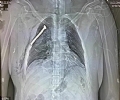

比利时首都布鲁塞尔22日发生连环恐怖袭击,机场离境大楼发生自杀式炸弹袭击后,市中心欧盟总部附近的地铁站也发生爆炸,造成30多人死亡,约100人受伤,其中许多人伤势严重。